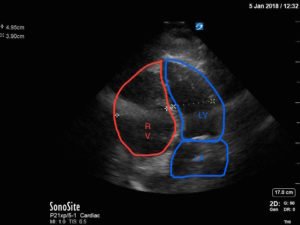

Bedside echocardiography four chamber view revealed enlarged right ventricular (RV) to left ventricular (LV) ratio (greater than 1) on apical four-chamber view (see red and blue outlines respectively). The right atrium is not clearly delineated in this image and therefore is not outlined. One can also rule out a large pericardial effusion as the cause of her dyspnea, since there is no large hypoechoic collection surrounding the heart on either four- chamber view or parasternal long view.

Point of care ultrasound is a powerful tool that can aid in the diagnosis of undifferentiated dyspnea. Right ventricular size is one parameter that can signify right heart strain possibly due to an increase in resistance in the pulmonary vasculature. The normal RV should be approximately two-thirds the size of the left ventricle. Any RV between two-thirds and equal to the size of the LV is considered moderately dilated, and any RV greater in size than the LV is considered severely dilated.1,2 The RV to LV size ratio is best measured from the apical four-chamber view. Right ventricular shape will also change as afterload increases in the pulmonary circuit. As pulmonary vascular resistance increases, the RV (which has significantly less myocardium and thus greater compliance as compared to the LV) begins to lose its typical triangular shape and takes on a more rounded appearance.3 Likewise, the intraventricular septum becomes flattened during early diastole due to higher RV:LV pressures causing the LV to take on a “D” shaped appearance. These findings, collectively referred to as signs of “right heart strain,” typically improve with resolution of the clot burden.4